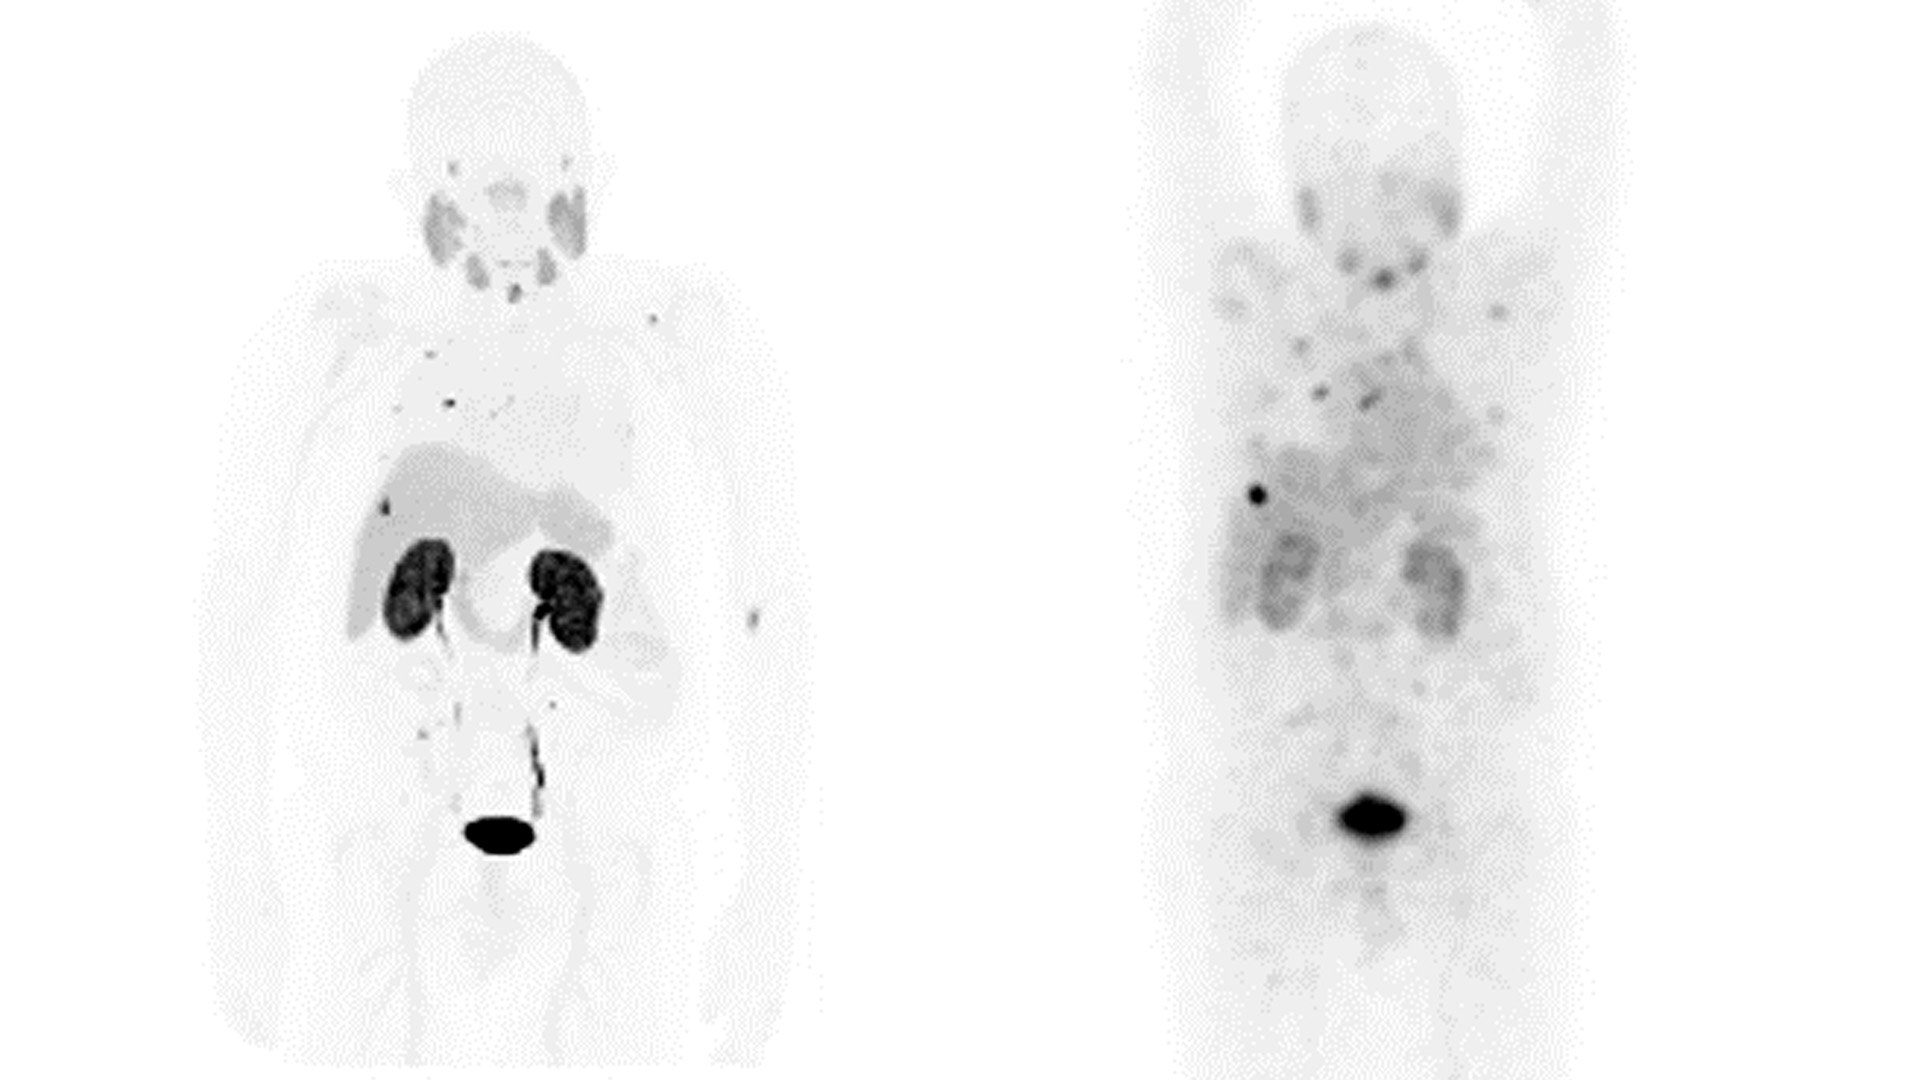

DIAGNÓSTICO

A GE HealthCare é pioneira nas soluções que permitem sensibilidade e confiança no diagnóstico inigualáveis.

Nosso portfólio dedicado de soluções de diagnóstico por imagem voltadas para Theranostics foi projetado especificamente para atender às necessidades dos médicos e de seus pacientes, hoje e no futuro.

GERAÇÃO DE IMAGENS E MONITORAMENTO DA TERAPIA

A GE HealthCare está moldando o futuro de Theranostics hoje com soluções precisas de geração de imagens e monitoramento e inovações na resposta ao tratamento.